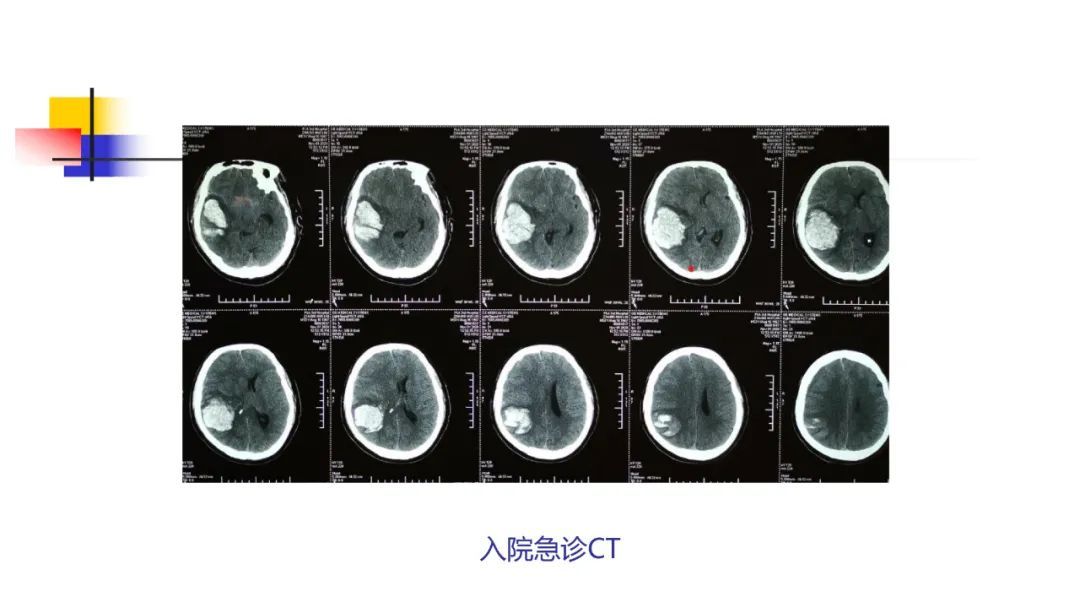

今天为大家分享的是《监测有道丨颅脑创伤-神经重症周刊》第249期,由中国人民解放军联勤保障部队第九八七医院神经外科张荣军主任团队带来的:重症脑出血术后继发颅内感染一例,欢迎观看、阅读。